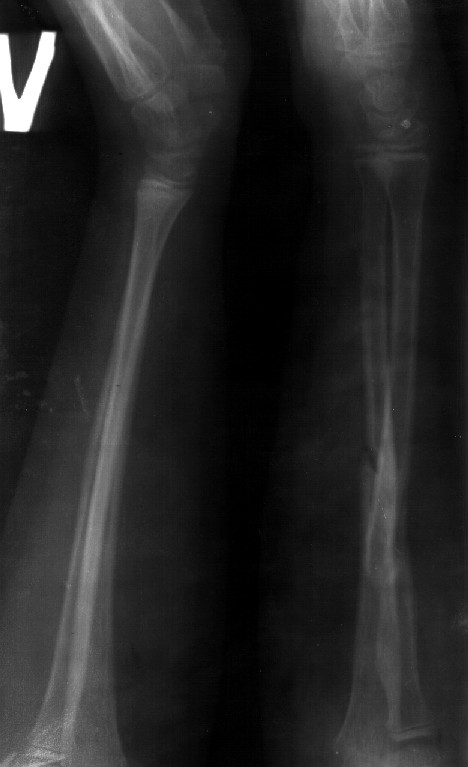

Сделал симметричные снимки с максимальной супинацией и пронацией при согнутом предплечье в 90 град. Объем ротационных движений 90-100 град.

С ув. Сергей Мелашенко

Снимок один сделан с супинацией, второй - оба предплечья в одинаково нейтральном положении. то есть по этим снимкам объем ротационных движений не оценить. Снимко в двух проекциях лучше и делать в среднем положении между пронацией и супинацией, то есть обе проекции в однм и том же положении, когда линия, проходящая через шиловидные отростки, идет в плоскости головки. Прошу прощения за усложнение простых вещей.

А для оценки ротации лучше сделать фото - дать пациенту зажать в кулаки одинаковые палочки (телескопы от апп. Илизарова идеальны), поставить... Впрочем, вот фото, чтобы все было понятно без слов. Локти к бокам пусть остаются прижатыми не только при супинации, но и при пронации.